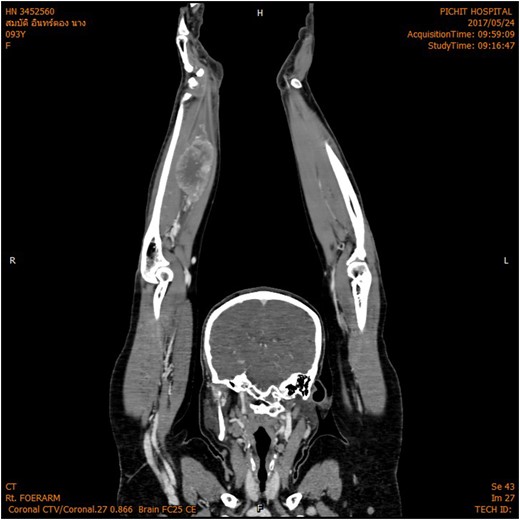

The magnetic resonance imaging (MRI) scan demonstrated a hypervascular mass with multiple feeding vessels located in flexure tendon of right forearm (Fig. 2). Ultrasound-guided biopsy revealed malignant poorly differentiated epithelioid neoplasm with clear cell feature and focal necrosis (Fig. 3). Workup distant metastasis prior operation chest X-ray and intra abdominal were cleared. Bone scan study shows the areas of increased radiotracer accumulation at right seventh of right rib posterolaterallly, L2, right sacroiliac region, proximal part of left humerus and proximal of right femur, multiple foci of osseous metastasis cannot be rule out.

MRI shown hypervascular mass with multiple feeding vessels located in flexure tendon of right forearm.

Here, we report a 53-year-old female with ASPS. To the best of our knowledge, her age is the oldest patient of ASPS in the English literatures. ASPS is usually a slow-growing tumor; however, in our case, patient presented with a rapidly growing lesion over a period of 5 months, which has not been described previously. ASPS often occur primarily in the lower extremities and trunk, our case is a rare case that occurs in upper extremity. Other rare locations of ASPS were reported such as intracranial, tongue and larynx. ASPS is hypervascular soft tissue sarcoma. As seen in our case, MRI studies also show hypervascular lesion and have many feeding vessels into tumor.